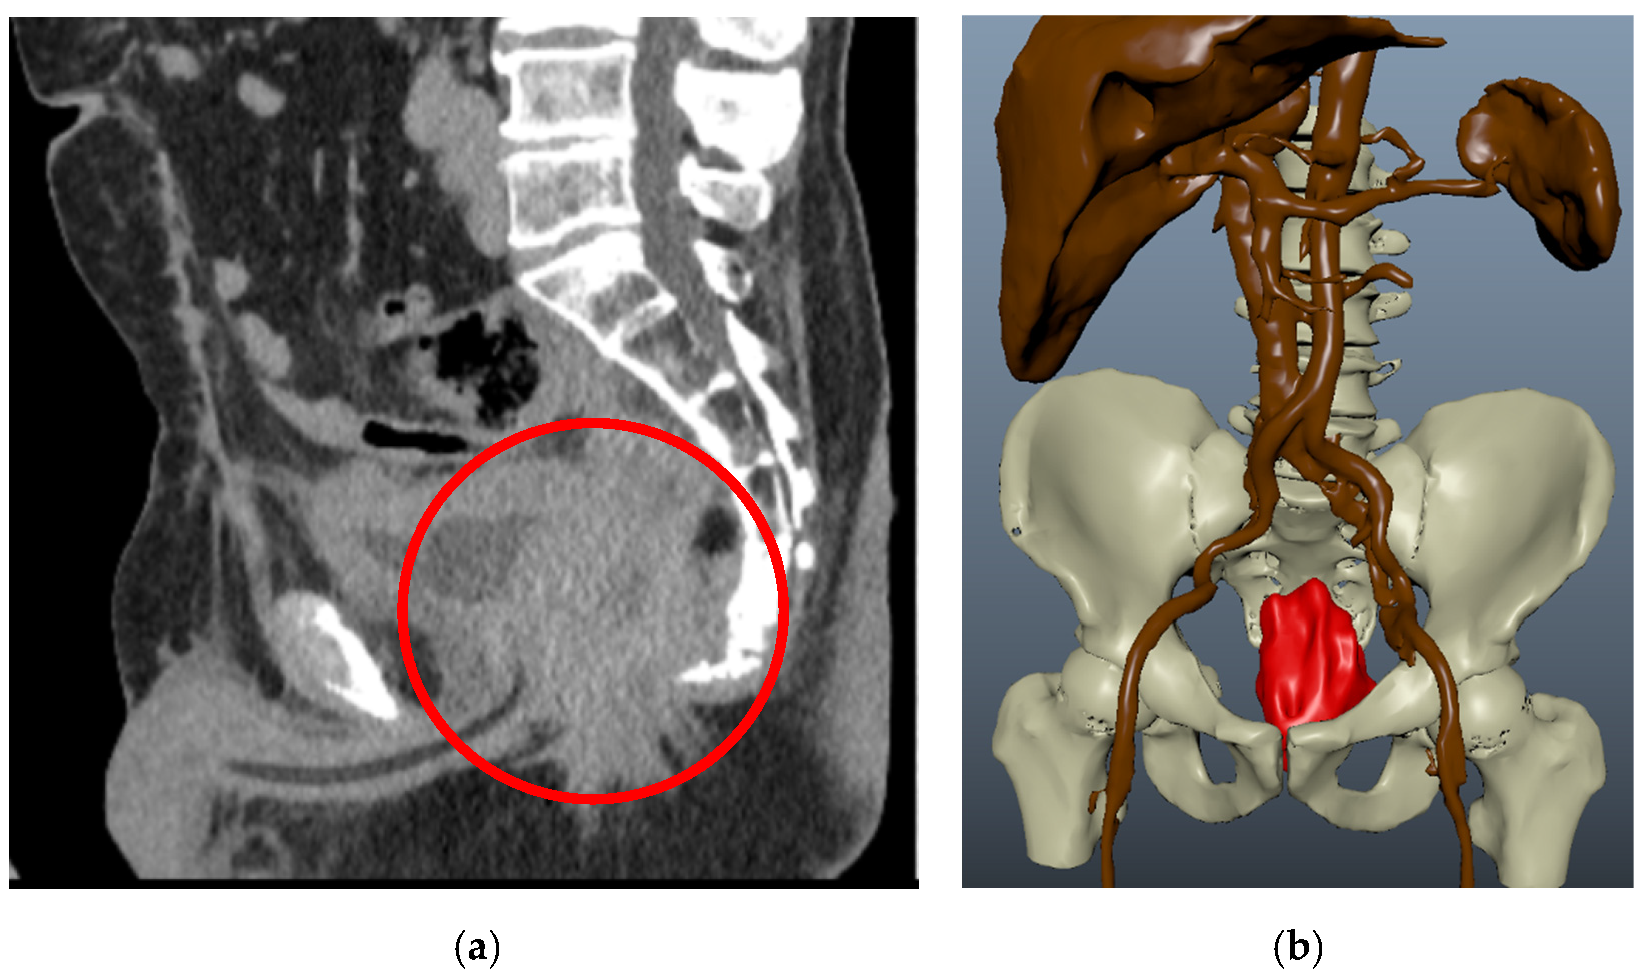

3.1. Clinical Experience in Cases with Invasive Markers

3.2. Clinical Experience in Cases with Noninvasive (Skinbased) Markers